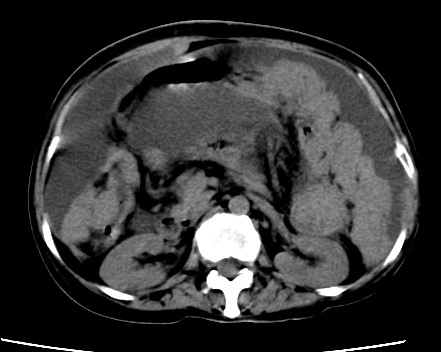

标题: CT23975:女61岁,腹部不适,明显消瘦

既往5年前卵巢癌行子宫及附件切除,右乳癌术后一年,考虑腹膜转移?

大量腹水,考虑腹膜转移。肝脏低密度灶。1囊肿,2转移。

1)结合病史,考虑腹膜及网膜转移瘤。2)肝脏多发性低密度灶,不排除转移瘤。3)大量腹水。

考虑卵巢癌行子宫术后复发,并肝、腹腔 、大网膜转移可能性大。

大量腹水。